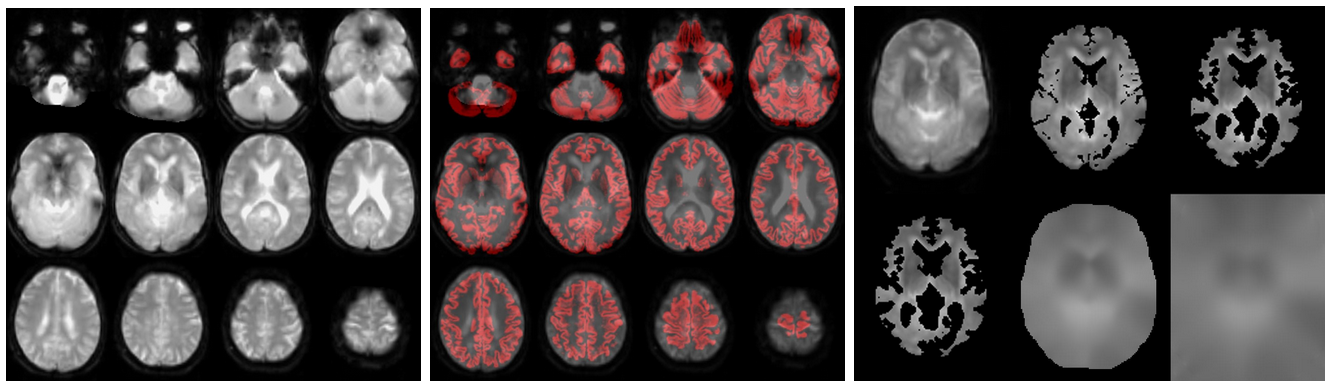

If an M0 scan exists (from left to right):

//Population/M0Check/Tra_noSmooth_M0_*_ASL*.jpgfor the inspection of M0//Population/M0_Reg_ASL/Tra_Reg_pGM_noSmooth_M0_*ASL*.jpgfor the M0->T1w registration (pGM in red)//Population/M0_Reg_ASL/M0_im_proc_*.jpgfor processing of M0 into a smooth bias field (masking & smoothing). Verify that the mask correctly removes the CSF & extracranial signal, to avoid smoothing of this into the M0 bias field.